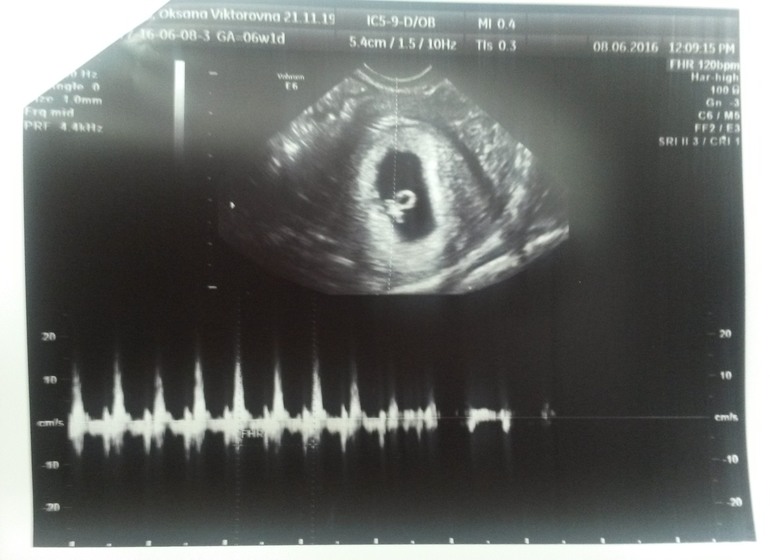

А сегодня с мужем ходили на первое УЗИ, так сказать для подтверждения и успокоения себя) Я так волновалась, что голос мой был тихий, пальцы тряслись, муж обнимал и подбадривал, говорил, что все хорошо! За это ему особое спасибо

Врач УЗИ очень хорошая девушка, все прокомментировала, обо всем рассказала. Я до этого смотрела в интернете фото УЗИ на эти сроки и знала, что я должна увидеть) Вот, значит, датчик и ...вот моя малявочка!

Вроде такие маленькие 0,66 см, но уже есть сердце! И оно бьется!!!

Врач включила звук и мы с мужем услышали ЕГО!!! 154 удара в минуту!

Это не передать словами! Я расчувствовалась! Врач увидела мои слезки и сказала, что плакать нельзя, иначе будет тонус, которого сейчас нет! Все у нас хорошо. По размерам и всем остальным параметрам соответствуем срокам. Крепимся по задней стенке, значит, сказала, живот появиться позже. Мало в это верю почету-то)))